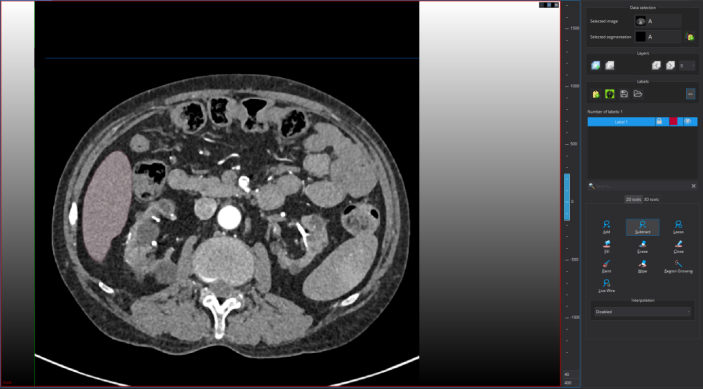

Step 2: 导入图像。即手动将亟待标注的”.nii.gz”文件拖动到下图区域

Step 3: 调节窗宽窗位。有两种方式,手动设置及滑动调节。如果标注肝肿瘤,我手动将窗宽窗位调节到[40-400]

Step 4 进入一个窗口进行标注: 进入单个视图画面更大,更有利于标注。

如果标注完成也可退出此视图:

尽管上图标注看似不错,但仍可以进一步精细修改。鼠标指向标注目标区域,按住鼠标右键进行放大

精修后的可视化如图:

接下来,需要对每个切片进行逐层标注,上面仅仅标注第372层切片面,标注者需要对每个切片逐一标注,切换切片的方式为:点击框图中的上下切片切换按键即可